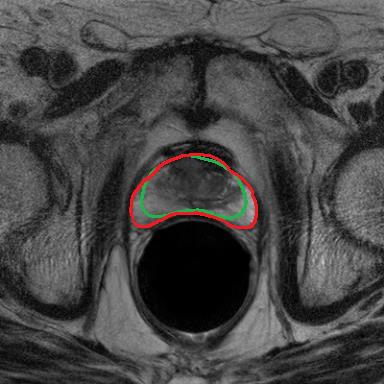

Modern deep neural networks struggle to transfer knowledge and generalize across diverse domains when deployed to real-world applications. Currently, domain generalization (DG) is introduced to learn a universal representation from multiple domains to improve the network generalization ability on unseen domains. However, previous DG methods only focus on the data-level consistency scheme without considering the synergistic regularization among different consistency schemes. In this paper, we present a novel Hierarchical Consistency framework for Domain Generalization (HCDG) by integrating Extrinsic Consistency and Intrinsic Consistency synergistically. Particularly, for the Extrinsic Consistency, we leverage the knowledge across multiple source domains to enforce data-level consistency. To better enhance such consistency, we design a novel Amplitude Gaussian-mixing strategy into Fourier-based data augmentation called DomainUp. For the Intrinsic Consistency, we perform task-level consistency for the same instance under the dual-task scenario. We evaluate the proposed HCDG framework on two medical image segmentation tasks, i.e., optic cup/disc segmentation on fundus images and prostate MRI segmentation. Extensive experimental results manifest the effectiveness and versatility of our HCDG framework.